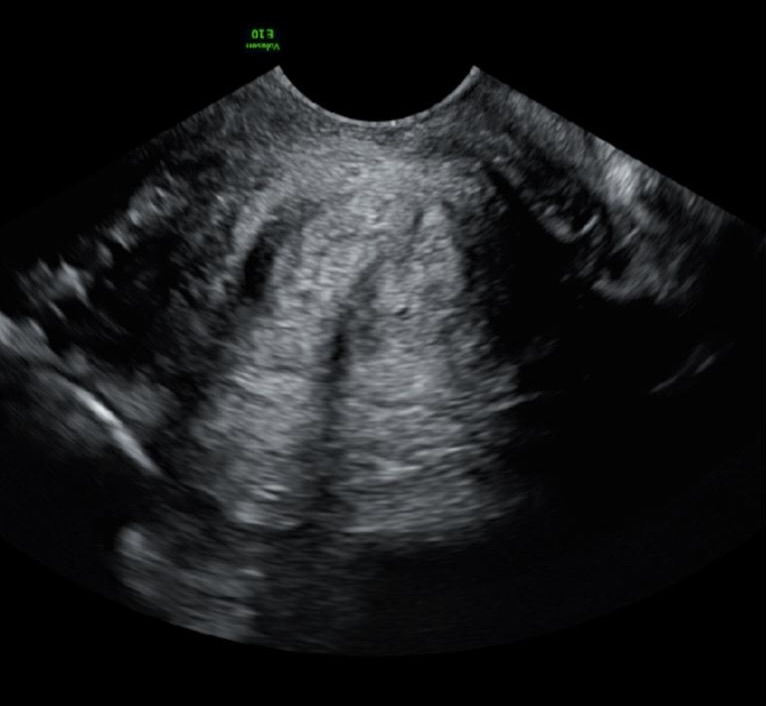

3. Underdeveloped lower uterine segment

At early gestations, less than 20 weeks, the lower uterine segment is not always fully developed and can mimic a long cervix. It is important therefore to make sure the internal os is correctly identified. Identifying the cervical glands and bladder angle as landmarks can help with this (Figure 1).

Figure 1. Example of an underdeveloped lower uterine segment, red arrows indicate underdeveloped lower uterine segment.